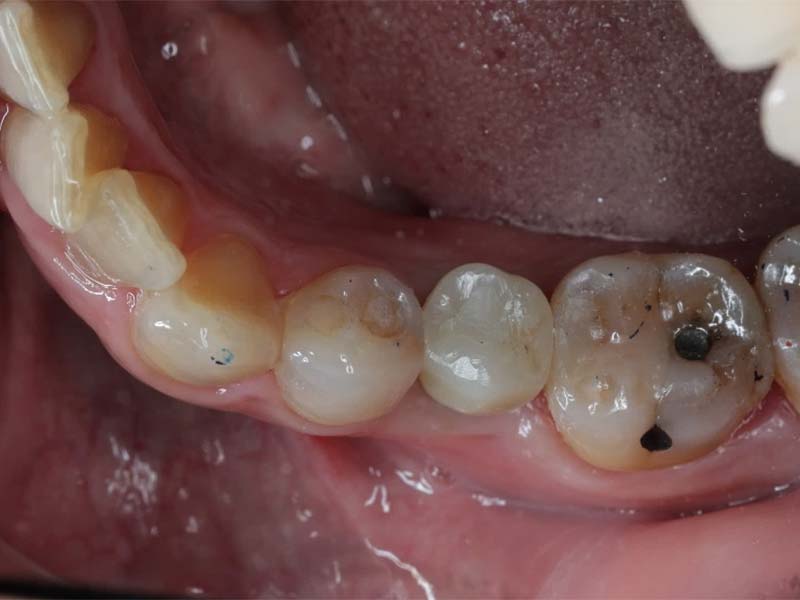

拔牙前

植牙案例分享